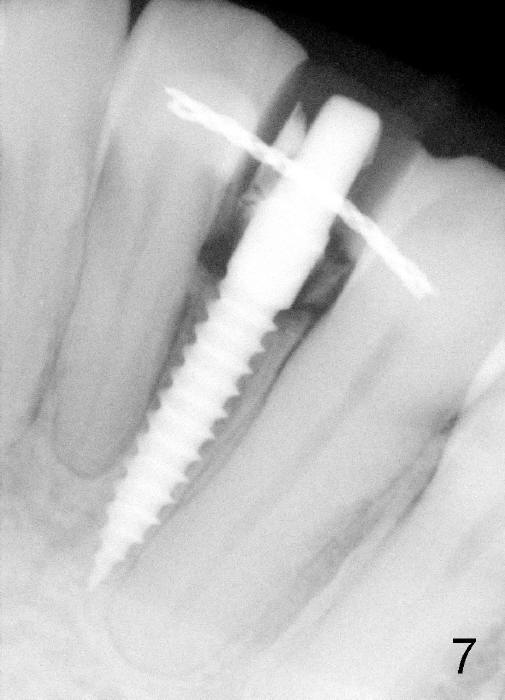

Within the first several days postop, the patient reports mild tenderness from one of the neighboring teeth.  Otherwise she is doing fine.  Again due to finance, she does not return for restoration for more than 1 year.  PA taken 10 months postop shows that there is no abnormality (Fig.7).  In fact bone resorption occurs gradually over 2 years 2 months postop, manifested as the 1st thread supracrestal (Fig.8 <).  When the 1-piece implant is reprepped for impression 2 years 2 months postop, the micro threads are found apical to the prep margin (Fig.9).  The nervous patient has had occasional tooth sensitivity 5 years postop.  A narrower implant is more suitable for this case (2.0 or 2.5 mm).